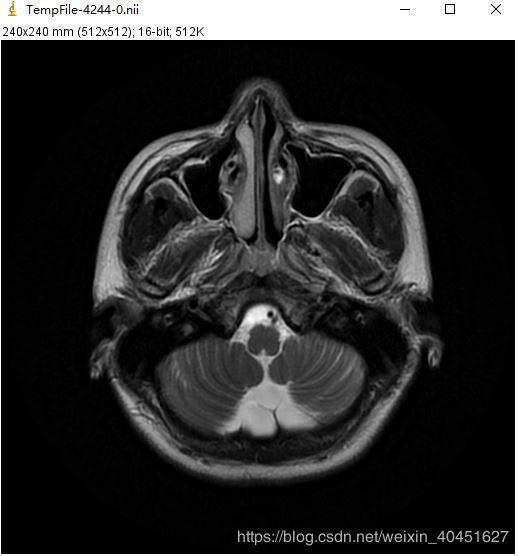

同一張Dicom文件使用sitk.Show()得到的效果如下圖:

除此之外,ImageJ還有一個Tool Bar 支持對圖像的進一步處理:

可見,SimpleITK的可視化要比上面介紹的強大很多,不僅可以實現單張圖像的可視化以及圖像處理,還可以同時對整個序列的圖像進行統一處理.